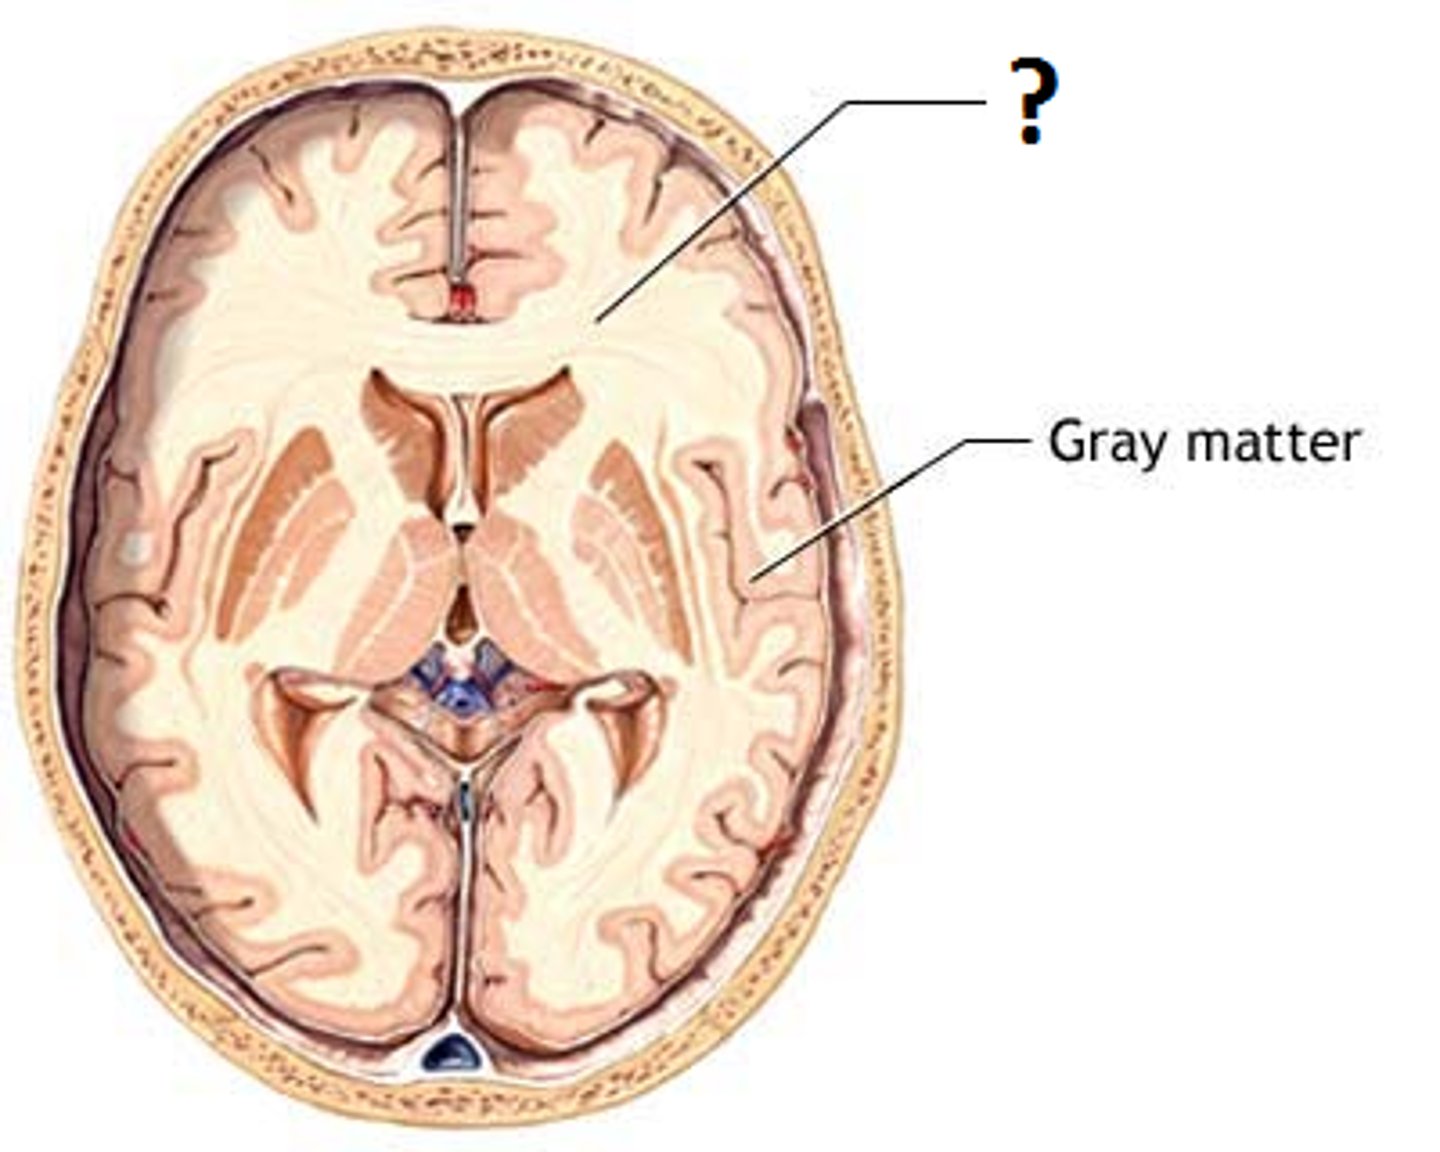

Gray matter

-The seat of neurosomas, dendrites, and synapse

-Dull color due to little myelin

-Surface of brain

-Forms nuclei deep within brain

White mater

-Bundles of axons

-Lies deep in brain

-Pearly white color from myelin